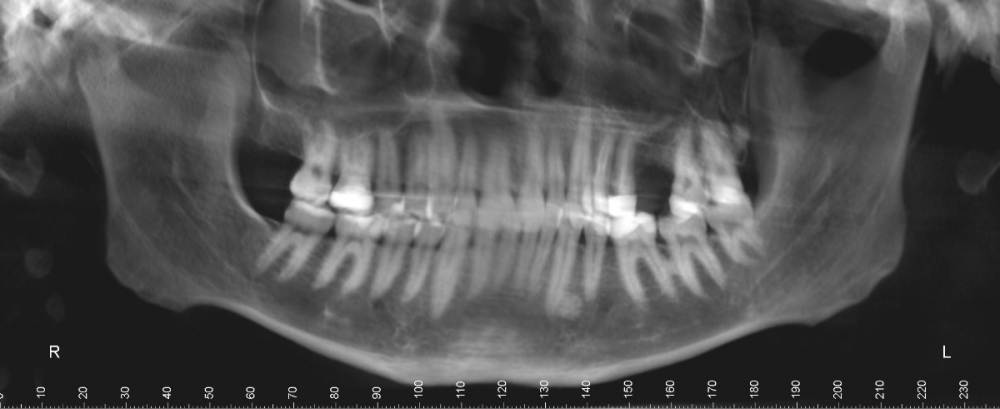

В общем нашел  врача-ортодонт, сделал снимок ортодонт-3 в одном центре и вот сегодня со снимками посетил врача.  Врач сказал, что только в комбинации с челюстной лицевой операцией можно, что то исправить. Подскажите, есть смысл идти к другому специалисту на консультацию что бы все таки без операции? ( Операцию делать не хочу)

оптг.jpg